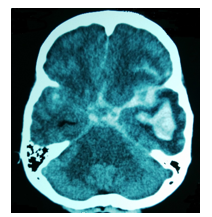

• Skull fractures

•High likelihood of  subdural/subarachnoid  haematomas

•More likely to have  multiple subdural  haematomas of  different ages

•More extensive retinal haemorrhages

•Disagreements on the so called SBS (shaken baby  syndrome) triad of injuries-subdural haematomaretinal haemorrhage, cerebral oedema